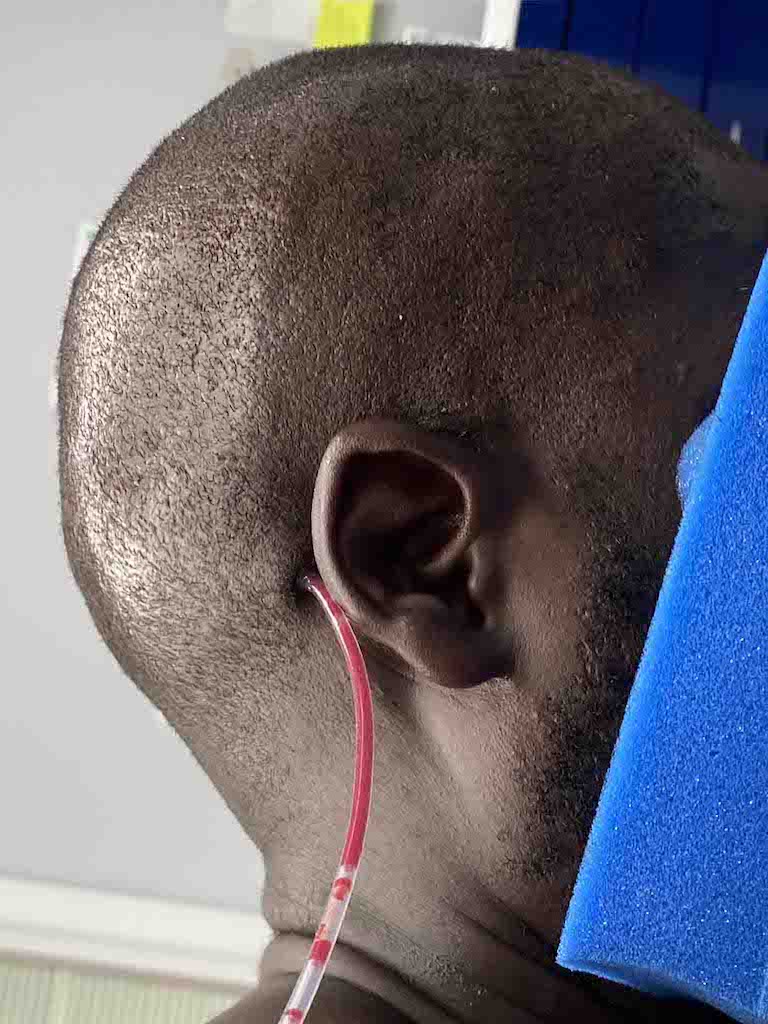

Patient 8

Desire to reduce prominent bone protrusion on the back of his head.

Occipital knob skull reduction through a direct bone burring technique.